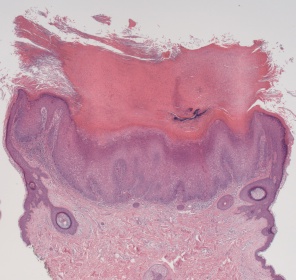

Histology [9]

There is no single histological finding that can characterize keratoacanthoma. Rather, histologic diagnosis requires a constellation of findings:

- Exoendophytic lesion composed of layers of well-differentiated squamous epithelium resulting from acanthosis

- Central keratin-filled crater that may enlarge as the lesion evolves and matures

- Larger mature keratinocytes are found towards the center of tumor cell nests

- Cytoplasm of large keratinocytes give eosinophilic hue on H & E stain.

- Buttressing (lipping) of the lesion edges around the central crater, creating a symmetrical appearance

- Adjacent dermis may contain small micro abscesses composed of mixed inflammatory infiltrate (eosinophils and neutrophils)

Note: Histologic features that favor keratoacanthoma over squamous cell carcinoma include hemispheric flask like shape with overhanging edges and central keratin plug